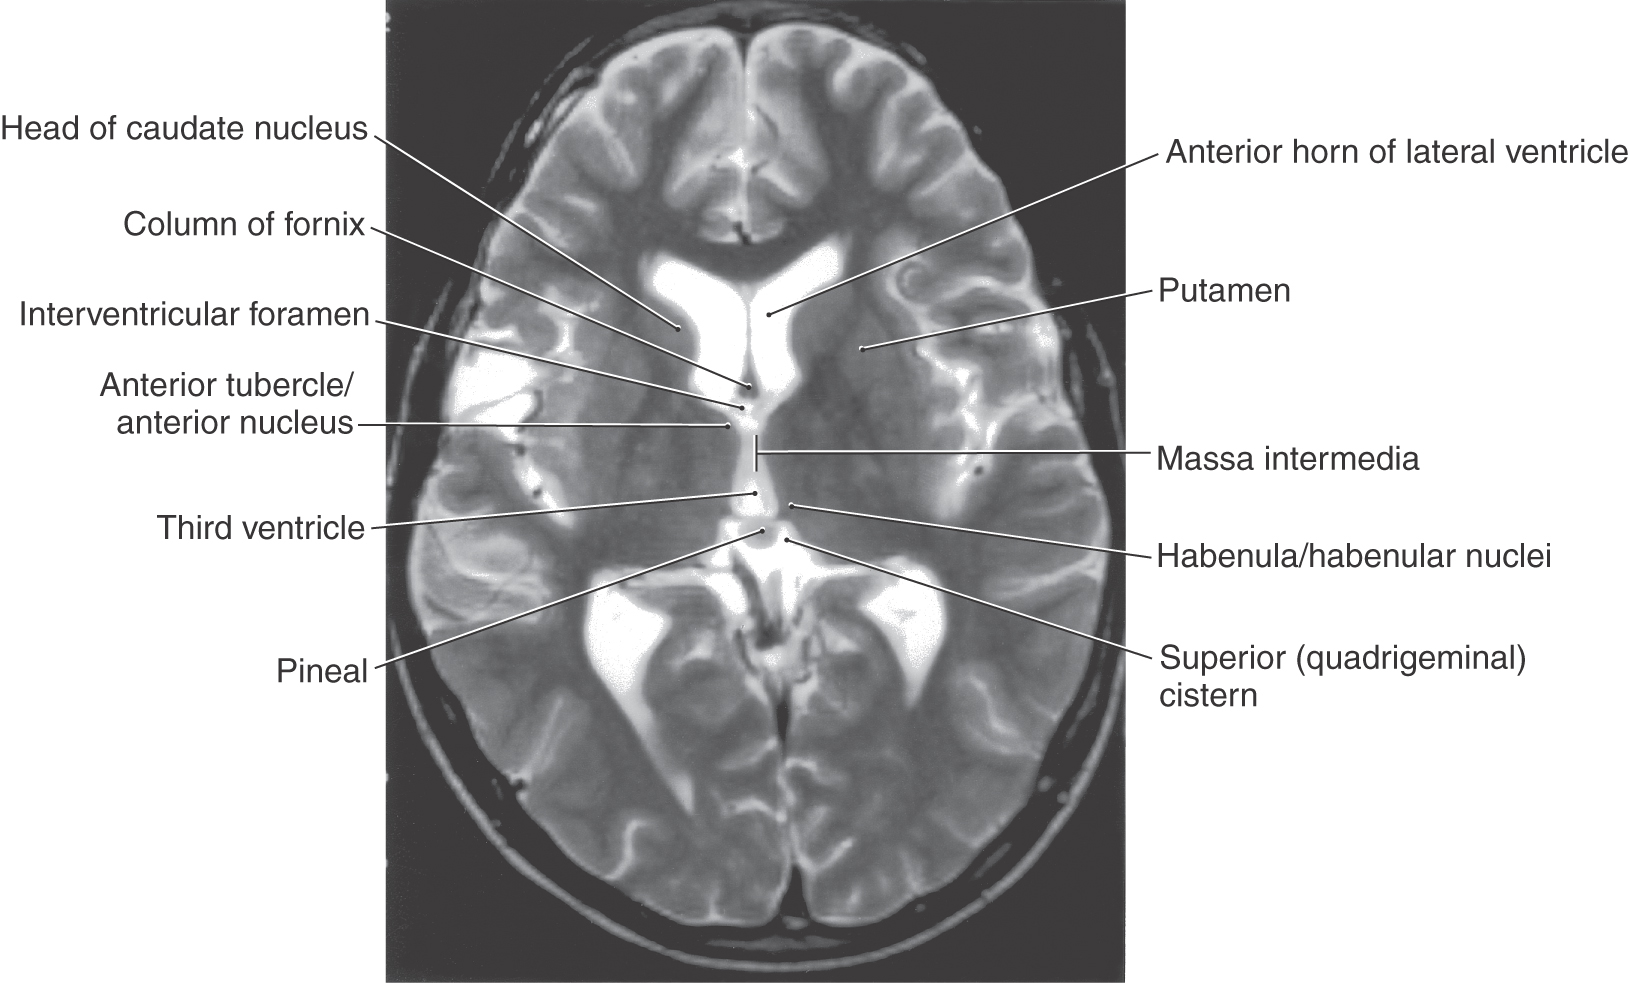

A shallow groove appears in the wall of the third ventricle and extends rostrally from the developing cerebral aqueduct to the ventral edge of the interventricular foramen (Fig. 15-1A, B). This groove, the hypothalamic sulcus, divides the alar plate into a superior (dorsal) area, the future dorsal thalamus, and an inferior (ventral) portion, the future hypothalamus. The third ventricle, which is the vertically oriented, midline space of the diencephalon, is continuous with the paired lateral ventricles via the interventricular foramina (foramina of Monro) (Figs. 15-1B and 15-2). The dorsal thalamus on each side of the third ventricle increases rapidly in size and, in about 80% of patients, will partially fuse across the space of the third ventricle to form the massa intermedia, or interthalamic adhesion (Figs. 15-2 to 15-4). The epithalamus develops from the caudal portion of the roof plate (Fig. 15-1B). By the seventh week, a small thickening of the roof plate forms. It gradually increases in size and evaginates to form the epiphysis, which develops into the pineal gland of the adult (Figs. 15-2 to 15-4). The portion of the roof plate immediately rostral to the epiphysis gives rise to the habenula, a small thickening in which the habenular nuclei will develop (Figs. 15-2 and 15-4).

Figure 15-2. Axial T2-weighted magnetic resonance image showing the interventricular foramen, the massa intermedia, the area of the habenula, and the pineal in the superior cistern. The interventricular foramen is the space (containing a small portion of choroid plexus) located between the column of the fornix and the anterior tubercle of the thalamus. The major nuclei of the dorsal thalamus in an axial plane are shown in Figure 15-10.